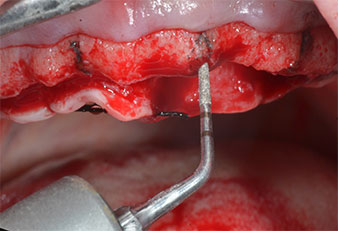

Un insert piézoélectrique diamanté de forme effilée (Piezomed I1) a été utilisé pour marquer les positions implantaires et effectuer la préparation pilote (Fig. 3). On a pris soin de travailler selon un mouvement ascendant et descendant, à puissance réduite, irrigation complète et basse pression (moins de 300g). Ensuite, un insert pilote (Piezomed I2A/I2P) a été utilisé pour l’agrandissement initial de 2mm du diamètre des sites implantaires (Fig. 4), suivi d’un insert de 3mm (Fig. 5).

Dans le cas présent, les inserts Z25P et Z35P n’ont pas été utilisés car l’os postérieur était relativement mou

et l’intervention sur celui-ci a été aisée avec le I3A/I3P.